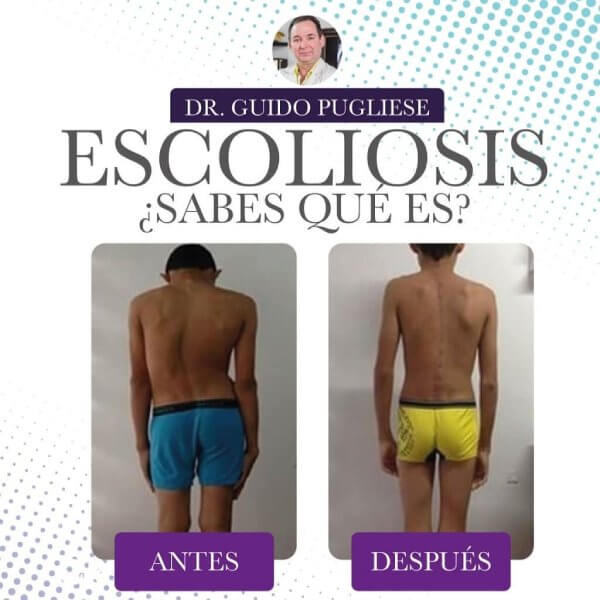

Ortopedista y traumatólogoOrtopedista de columna vertebralEscoliosis

Las especialidades de Dr. Guido Pugliese Casalins son: Ortopedista y traumatólogo, Ortopedista de columna vertebral, Escoliosis.

Presentaba una escoliosis desde niña que se me fue aumentando, apesar de que yo seguia todas las indicaciones de los medicos que me veian, progreso tanto que me daba pena usar ropa ajustada o vestido de baño. Otros medicos me decian que una cirugia era muy peligrosa porque podia quedar en silla re ruedas, y me recomendaron al Dr Guido una persona que habia operado de lo mismo, me anime y me someti a la cirugia. Desde ese dia mi vida cambio, me recupere rapidamente, hoy hago todas mis actividades normles y no me da pena ni usar vestido de baño. Gracias Dr Guido por cambiarme la vida !!!